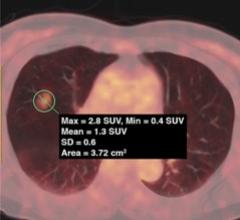

April 7, 2021 — Body composition information derived from routine chest computed tomography (CTs) can provide important ...